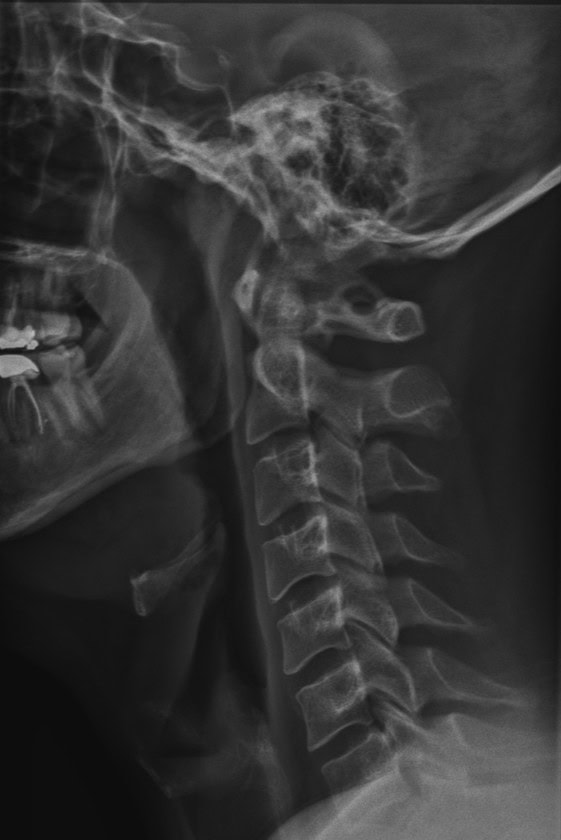

Kaylan’s journey with Maximize Chiropractic began back in 2015, when he came to us seeking relief from lower-back pain caused by an old snowboarding injury, along with persistent neck discomfort. Over the years, he dedicated himself to improving his health, including completing several sessions of Cranial Facial Release (CFR).

Through consistent care, Kaylan experienced significant improvement in his respiratory system, along with noticeable progress in his lower-back function, sleep quality, and overall energy levels. His commitment to his well-being has made a remarkable difference in his daily life.